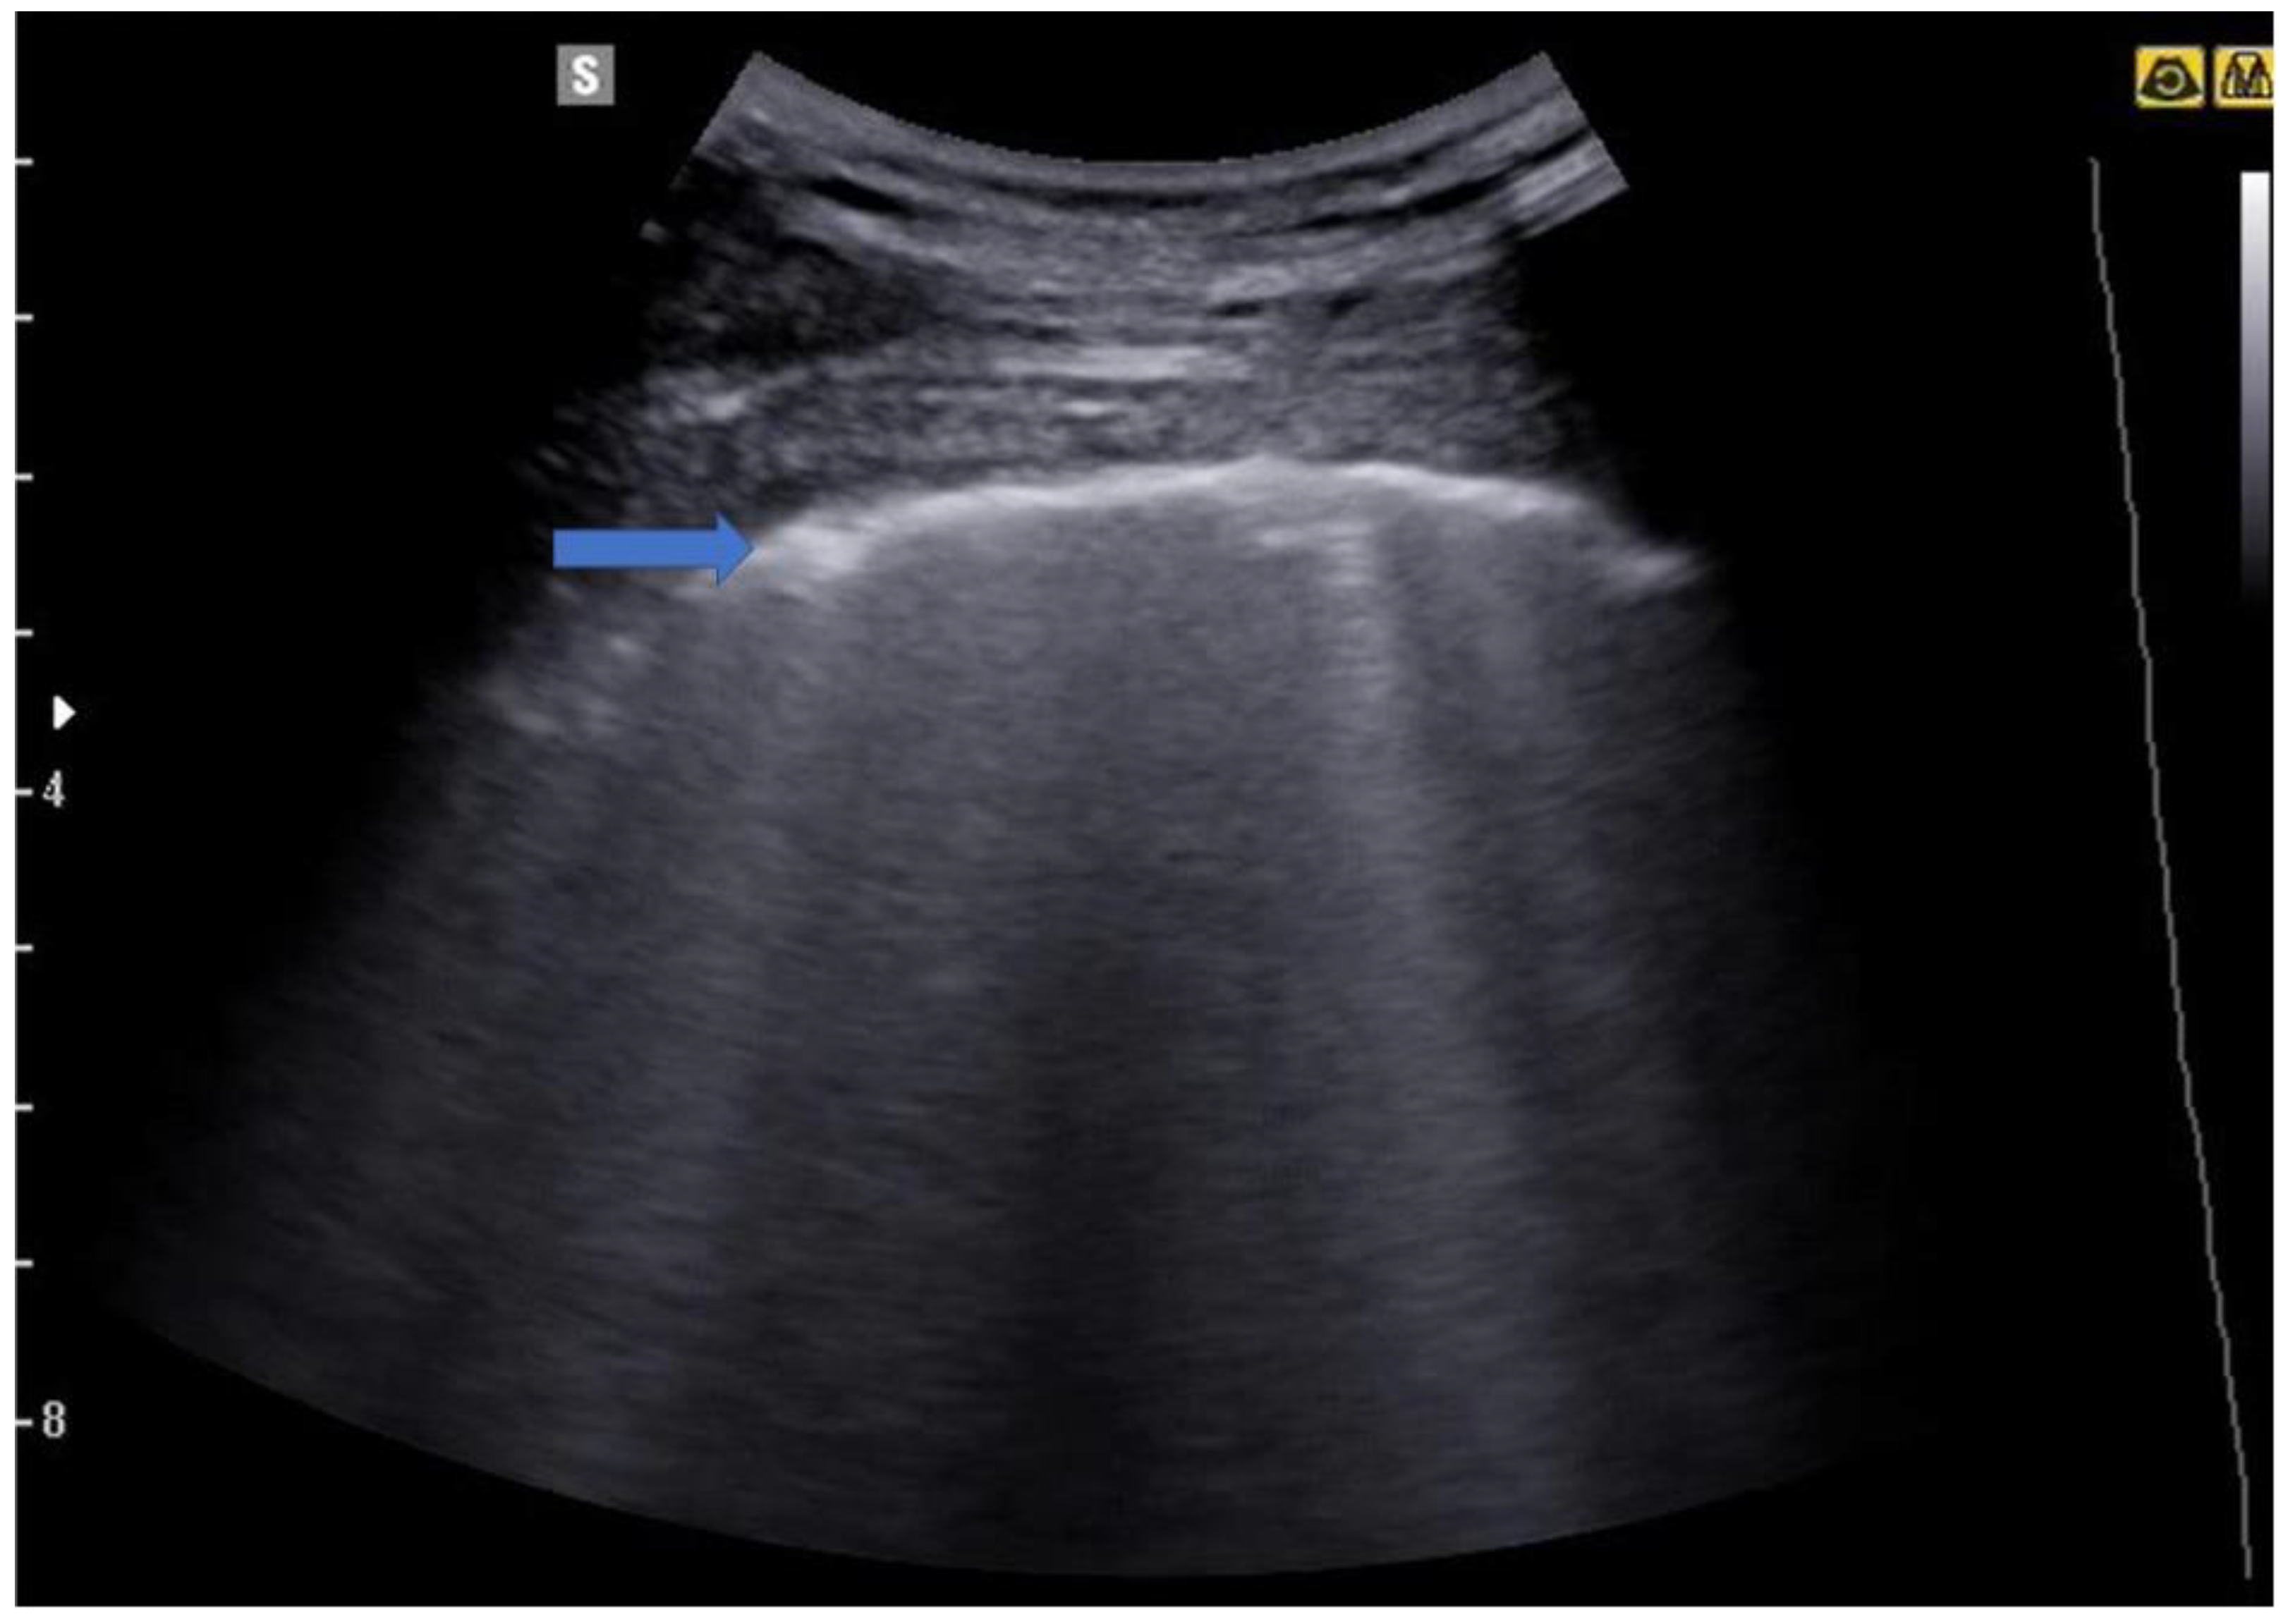

5.2. Lung Consolidations

5. From the B-Lines to the Pathological Lung